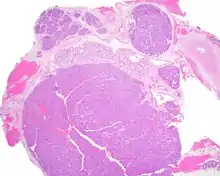

A hematoxylin and eosin stained slide of canalicular adenoma showing large canaliculi

The growths often contain are often small bight squamous balls, or morules. They also tyipcally contain a well-developed supporting tissue - a fibrous stroma - which is rich in hyaluronic acid and chondroitin sulphate.[1] In a few cases, the growths may contain small calcium deposits or microliths. Although it is seldom necessary, a pathologist can confirm the existence of canalicular adenoma through immunohistochemistry studies, with the cells reacting with pancytokeratin, S100 protein and SOX10, with a delicate GFAP reaction around the periphery.[5][1][6][7] Although it is a benign tumor, a positive diagnosis of canalicular adenoma may be necessary to exclude the existence of other medical conditions such as a basal cell adenoma, pleomorphic adenoma, adenoid cystic carcinoma, and polymorphous adenocarcinoma.